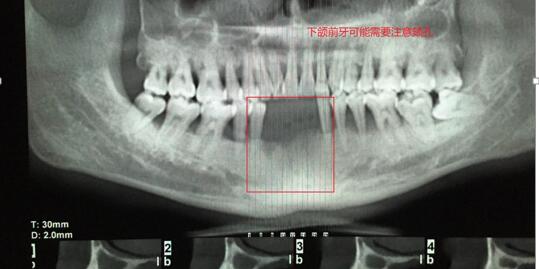

何XX,男,18歲 主訴:左右下前牙缺失3月余,影響美觀。 現(xiàn)病史:左右下前牙3個(gè)月前因重度牙周炎在我院頜面外科拔除,現(xiàn)要求種植修復(fù)。 既往史:否認(rèn)系統(tǒng)病史。 檢查: 31、32、41、42、43缺失,拔牙創(chuàng)愈合良好,缺失間隙近遠(yuǎn)中寬度18mm,頜齦距離正常,頰舌向?qū)挾燃s8mm。33、44牙體無(wú)明顯異常和傾斜,叩(-)松(-),咬合關(guān)系正常。全口牙結(jié)石(I)度,牙齦紅腫,可見(jiàn)牙槽骨水平吸收。 輔查: 口腔CBCT(錐形束CT)顯示全口牙槽骨水平吸收,43,32可用牙槽骨高度(牙槽嵴頂?shù)?約12-15mm,頰舌側(cè)寬度7mm,骨質(zhì)正常,無(wú)疏松影像。 診斷: 31、32、41、42、43牙列缺損。 治療計(jì)劃:種植...